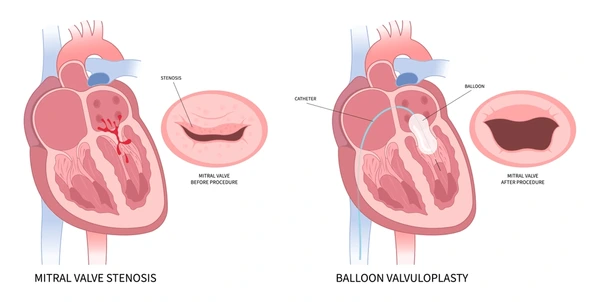

Value added benefits of the Balloon Mitral Valvuloplasty:

Ø Doctor consultation charges

Ø Lab tests and diagnostic charges

Ø Room charges inside hospital during the procedure

Ø Surgeon Fee

Ø Nursing charges

Ø Hospital surgery suite charges

Ø Anesthesia charges

Ø Routine medicines and routine consumables (bandages, dressings etc.)

Ø Food and Beverages inside hospital stay for patient and one attendant.

Extra benefits:

ü Interpreter

ü Visa assistance

Ø Site tourism of the city

Ø Follow up with the doctor

Ø Airport pick up and drop

Ø Free online consultation with the doctor

Ø Priority appointments with the doctor

Ø Room upgrade from sharing to private